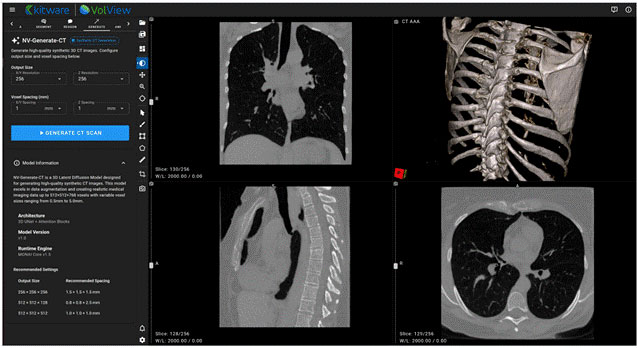

NV-Generate-CT/MR — 3D Synthetic CT and MR Generation

NV-Generate introduces the capability to generate realistic, anatomically consistent synthetic CT and MR volumes. In VolView, NV-Generate supports use cases such as data augmentation, educational content creation, and prototyping scenarios where non-protected health information (PHI) synthetic data is essential.